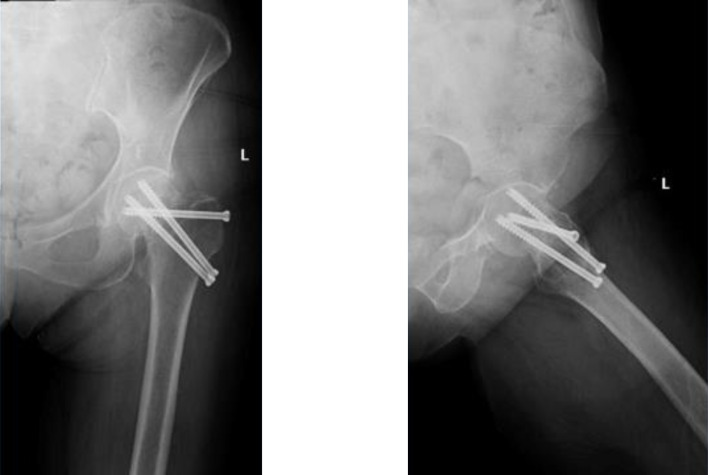

Introduction: Performing total hip arthroplasty (THA) after failed internal fixation of proximal femoral fractures (PFF) is known to be associated with high rates of complications. Dual mobility cups (DMC) are known to lower dislocation events in high-risk patients. Very few reports investigated the outcomes of THA using DMC following failure of internal fixation for PFF.

Methods: This is a retrospective monocentric continuous study of 31 patients who underwent THA with DMC after failed internal fixation of PFF. The clinical assessment was based on the modified Harris hip score (mHHS) at the last follow-up. The complication rates and radiological analyses were recorded.

Results: The mean follow-up period was 5.96 ± 4.2 years. At the last follow-up, the mean mHHS was 92.9 ± 9.1 with 71% of the patients describing their operated hip as a forgotten hip. No dislocation or aseptic loosening events were noted. One patient developed a septic loosening of the implant. No significant radiological changes were recorded. Sixteen stems (51.6%) were placed in a neutral position, 13 (42%) in valgus (2.74 ± 1.72°), and 2 (6.4%) in varus (6.94 ± 2.02°).